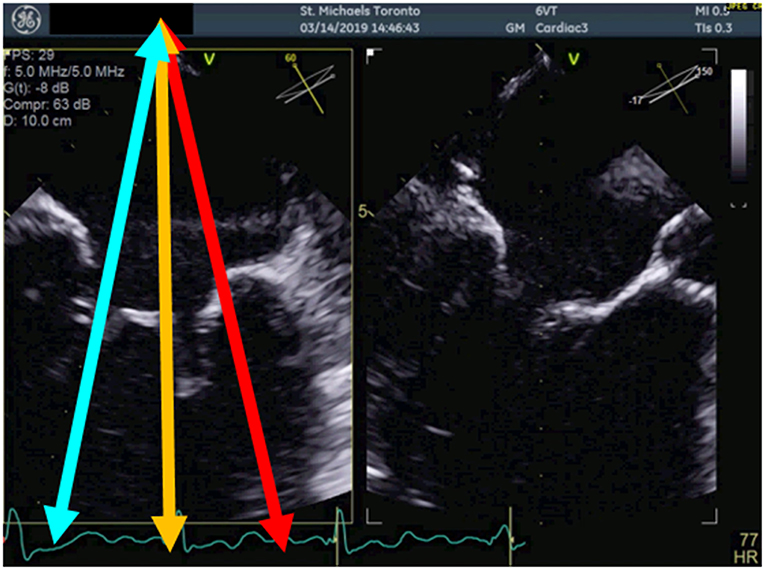

Transesophageal echocardiography (TEE) is the mainstay for MR intervention screening because of its key role in intraprocedural guidance. A careful examination of the mechanism of MR and quantitative assessment of MR degree of severity should be reported. In addition to the standard 2D echocardiographic views, utilization of advanced imaging is particularly helpful to determine the presence of anatomic abnormality. The use of multiplane imaging allows a systematic visualization of all MV scallops, from the medial to lateral aspects of the MV (Figure 1). An en-face view of the atrial side of the entire MV (surgeon's view) and adjacent structures is possible using 3D imaging. Flail and prolapse segments, the location of clefts, deep indentations, perforations and significant malcoaptation gaps may be more apparent and easier to visualize. In addition, MV area can more precisely be measured (Figure 2).

Figure 2. Measurement of the 3D mitral valve area (MVA) by transoesophageal echocardiography in a patient with severe MR; the MVA in this case was 5.48 cm2 indicating suitability for percutaneous mitral valve repair.